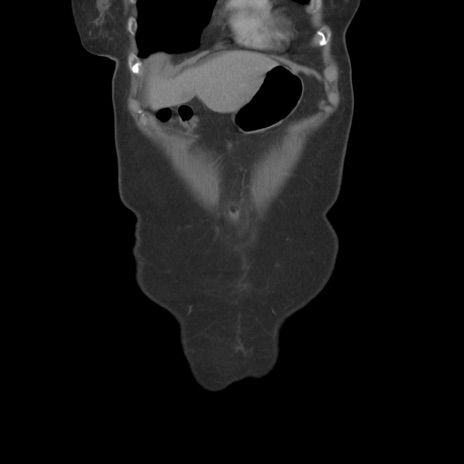

横断像